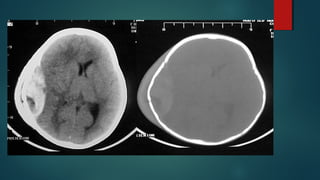

Este documento es el programa para un taller de imágenes del curso de emergencia 2015 impartido por el Dr. Víctor Delgado. El taller se centra en el uso de imágenes médicas para el diagnóstico y tratamiento de pacientes en coma traumático según la base de datos de Marshall. El Dr. Delgado es el único instructor repetido a lo largo del documento.